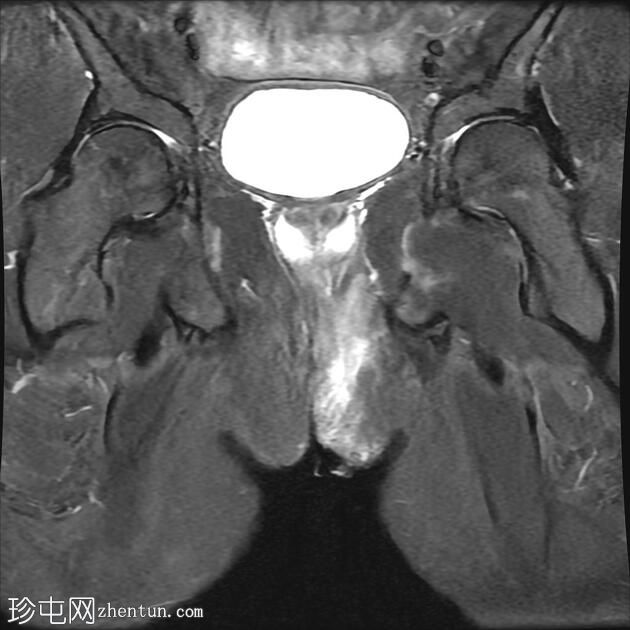

MRI

冠状位T2

脂肪饱和度

冠状位T1

C+脂肪饱和度

一条68毫米厚的强化通道始于左侧肛周区域,向上穿过肛门内外括约肌,在2点钟方向开口于肛管。

无脓肿形成。

MRI成像特征与所述左侧经括约肌肛周瘘相符。